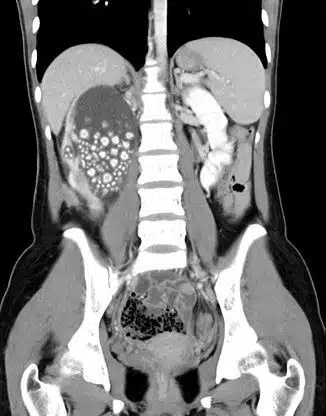

Exames iniciais revelaram um grave inchaço em seu rim direito, levando os médicos a realizar uma tomografia do abdome, onde revelou surpreendentes centenas de pedras no órgão.

Os médicos administraram-lhe antibióticos e realizaram um procedimento minimamente invasivo para remover as centenas de pedras nos rins acumuladas, que tinham uma aparência semelhante a “pãezinhos cozidos no vapor”, segundo os médicos.

Mais de 300 cálculos renais foram removidos da paciente, medindo entre 0,5 cm e 2 cm de diâmetro.